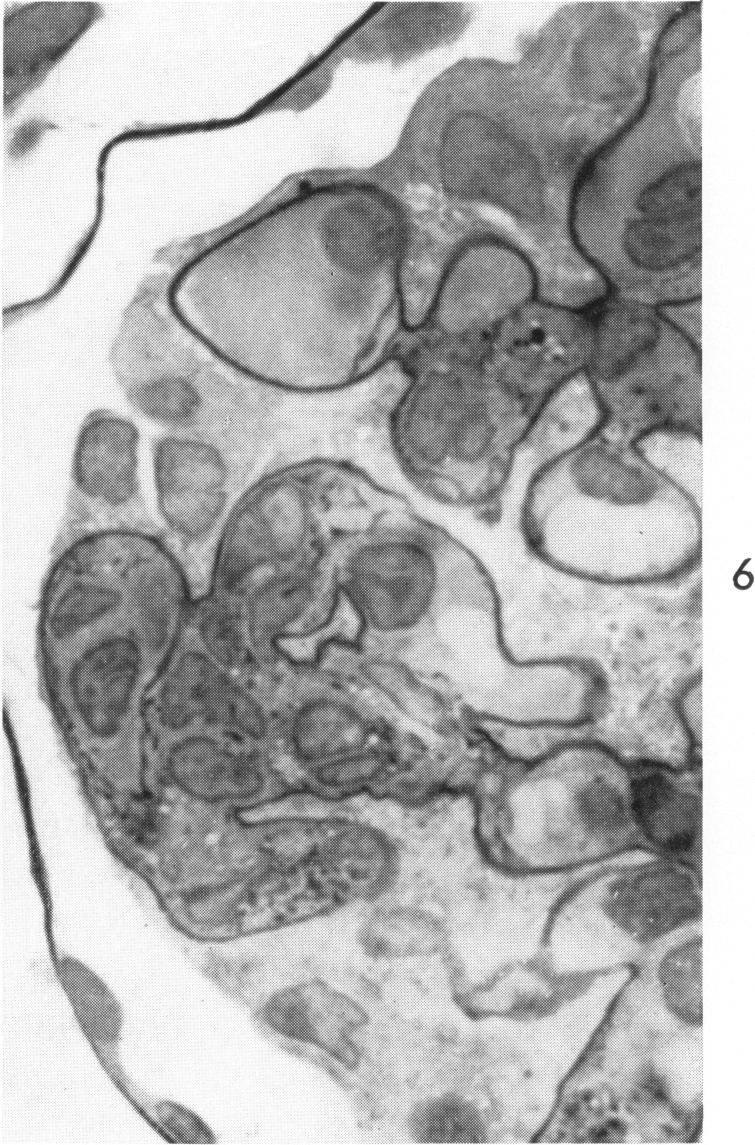

Nephrotoxic serum nephritis in the rat. Electron and light microscopic studies.

Am J Pathol. 1960 Dec;37(6):729-49.

PMID:13693531